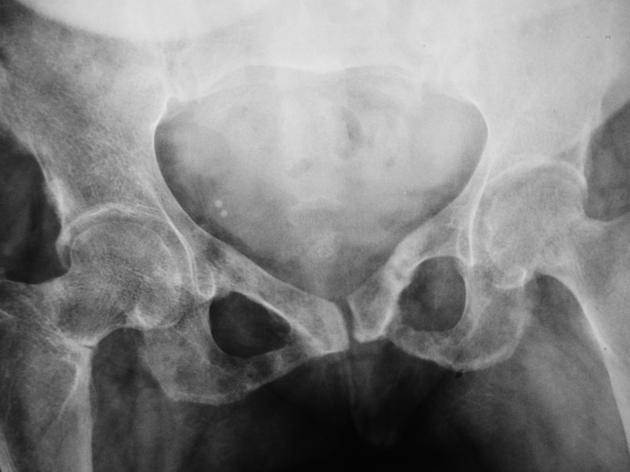

骨軟化症のレントゲン画像は以下のとおりです。

骨軟化症の画像検査では、小さな不完全骨折線(Looser’s zone)が特徴として見られます。